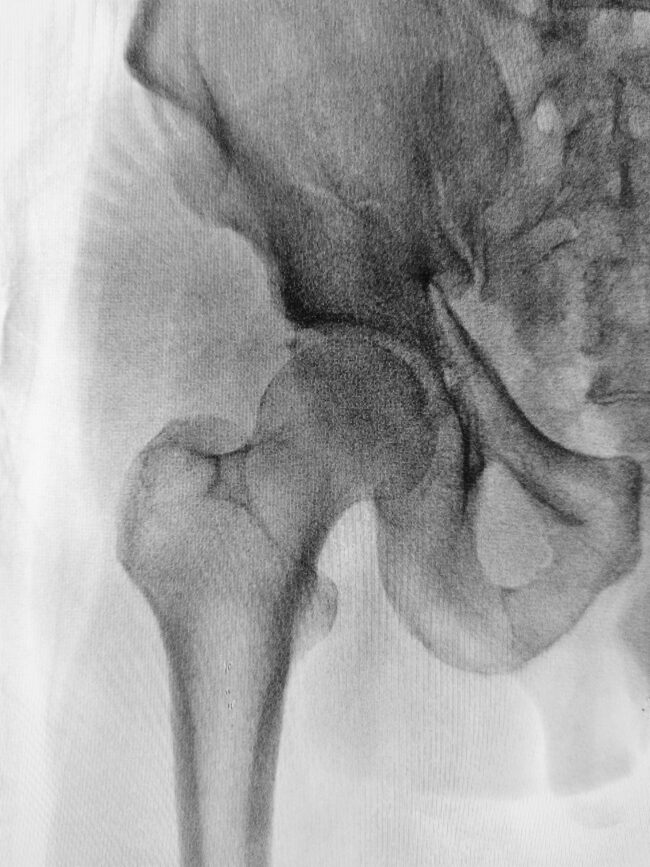

Recovery after a hip replacement: Tips and guidelines

If you’re experiencing difficulties walking or excruciating pain in your waist or hip area, your hip joint might need attention. These are some of the most commonly experienced symptoms of hip joint decay.  Luckily, medical advancement and cutting-edge operations can repair damaged joints: orthopedic surgeries like hip replacements are safe, advanced procedures that can help…